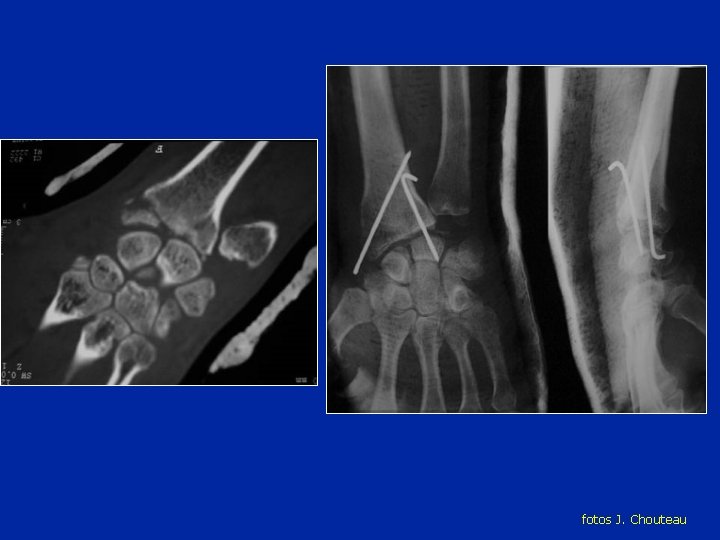

Luxación del semi lunar fotos J. Chouteau

Luxación del semi lunar Riesgo de necrosis

fotos J. Chouteau